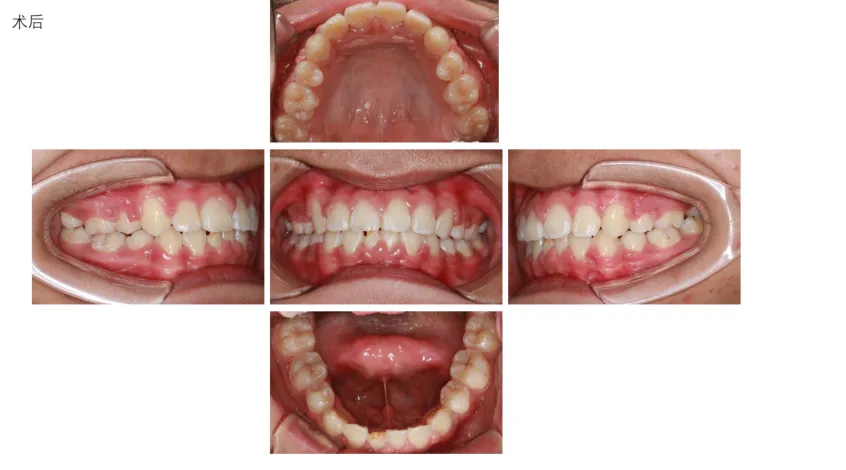

病例展示: